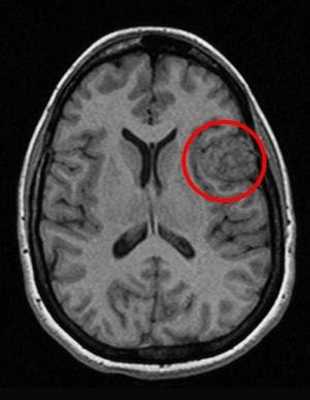

Перед вами - два снимка, сделанных в одном режиме. Снимок снизу - норма. Какое заболевание, в таком случае, есть на верхнем снимке? Чтобы понять это, нужно сравнить эти изображения. Явно видно отличие - на верхнем снимке в правой части головного мозга есть новообразование. Разница еще заметнее, если сравнить левую и правую части того же снимка.

Отметим его красной окружностью. Визуально оно представляет собой узел, неоднородный по окраске и отличающийся от серого и белого вещества головного мозга. В таких случаях, чтобы точно определить границы опухоли и определить её тип исследование повторяют с контрастом. Введение контрастного препарата в кровь через локтевую вену приводит к накоплению контрастного вещества в тканях опухоли - нормальные здоровые ткани его практически не накапливают. И мы получаем следующую картину, показанную на рисунке справа. Яркая окраска опухоли соответствует накопленному контрасту - теперь можно не только сказать, где опухоль, но и примерно определить, что это доброкачественная опухоль, так как она имеет четкие границы (злокачественные опухоли прорастают окружающие ткани, из-за чего границы будут размытыми и не такими четкими).